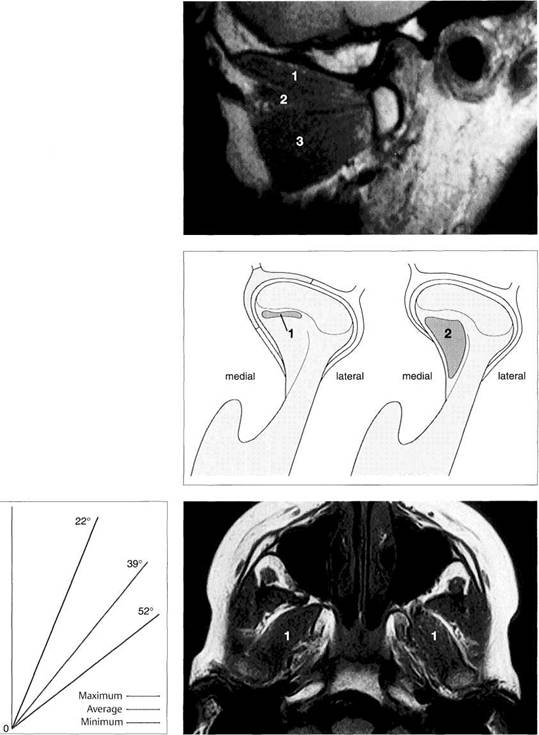

Positional Relationships of the Bony Structures

The position of the condyle relative to the articular protuberance has been a subject of controversy in dentistry for many years (Lindblom 1936, Pullinger et al. 1985). A well-defined condylar position oriented to the maximal occlusion is especially relevant to extensive dental treatment (Spear 1997). In the past, to transfer the jaw relations to an articulator the condyles were always placed in their most posterosuperior position because this relationship could be most easily reproduced (Celenza and Nasedkin 1979). Under purely static conditions the condylar position is dependent

upon the shape of the fossa, the inclination of the protuberance, and the shape of the condyle. In the 1970s this led to the assignment of a geometric centric position of the condyle in the fossa (Gerber 1971). However, the dimensions of the joint space are quite variable in both the sagittal plane (anterior, posterior, and superior) and the transverse plane (medial, central, and lateral) (Pullinger et al. 1985, Hatcher et al. 1986, Christiansen et al. 1987, Bumann et al. 1997). For this reason the concept of an anatomical orientation is untenable, and the radiographic techniques

Sagittal relationships

Macroscopic anatomical preparation showing the relation of the fossa, disk, and condyle to one another in the sagittal plane. Because the shapes of fossae and condyles vary so greatly, it is not possible to determine a universally applicable measurement of the condylar position. Although the physiological (i.e. centric) condylar position is defined as the most anterosuperior position with no lateral displacement (arrows), this position depends upon the basic neuromuscular tonus.

Frontal relationships

Macroscopic anatomical preparation showing the relation of the fossa, disk, and condyle to one another in the frontal plane. In this plane, too, there is no standard geometric arrangement of condyle and fossa because of the variability of the hard and soft tissues (Yung et al. 1990). In this preparation the disk (arrows) is displaced laterally. Structures of the bilaminar zone (1) can be identified in the medial portion of the joint. The close proximity of the joint to the middle (2) and inner ear (3) can also be observed.

Horizontal relationships

A right temporomandibular joint viewed from above showing the relation of the fossa, disk, and condyle to one another in the horizontal plane. The lateral portion of the joint is near the left border of the picture. Near the upper border a section through the external auditory meatus can be seen (1). The roof of the fossa has been removed. Near the center of the picture lies the transition from the pars posterior (2) to the bilaminar zone (3). The central perforation was created during sectioning, and through it can be seen the upper surface of the condyle (arrow).

Relationships in the frontal

plane

Schematic depiction of the joint space relationships in the frontal plane. A number of studies have reported that the dimensions found in the lateral, central, and medial parts may vary greatly (Christiansen et al. 1987, Vargas 1997). Although the lateral portion is affected more frequently by degenerative changes, the width of the joint space is usually least at its center (blue line).

Contours

on the temporal

surface of the joint

Schematic drawing (modified from Hassoetal. 1989) of the contours in the lateral (green), central (blue), and medial (red) regions of the joint. The entire protrusive functional path is represented as a convex bulge that can vary markedly as the result of regressive or progressive adaptation. Therefore, the loads borne by the lateral and medial portions of the joint during function are also influenced by the morphology of the articular protuberance (Oberg et al. 1971, Hylan-der 1979, Hinton 1981).

Relationships

in the medial

part of the joint

Schematic drawing (modified from Christiansen et al. 1987) of the positional relationships in the medial portion of a left temporomandibular joint. This finding also emphasizes the fundamental principles of physiological joint movements. As with all other joints, the temporomandibular joint has a passive "play" space in all directions and is thus not confined to any border position.

Average values: 1 = 3.4 mm; 2 = 4.4 mm